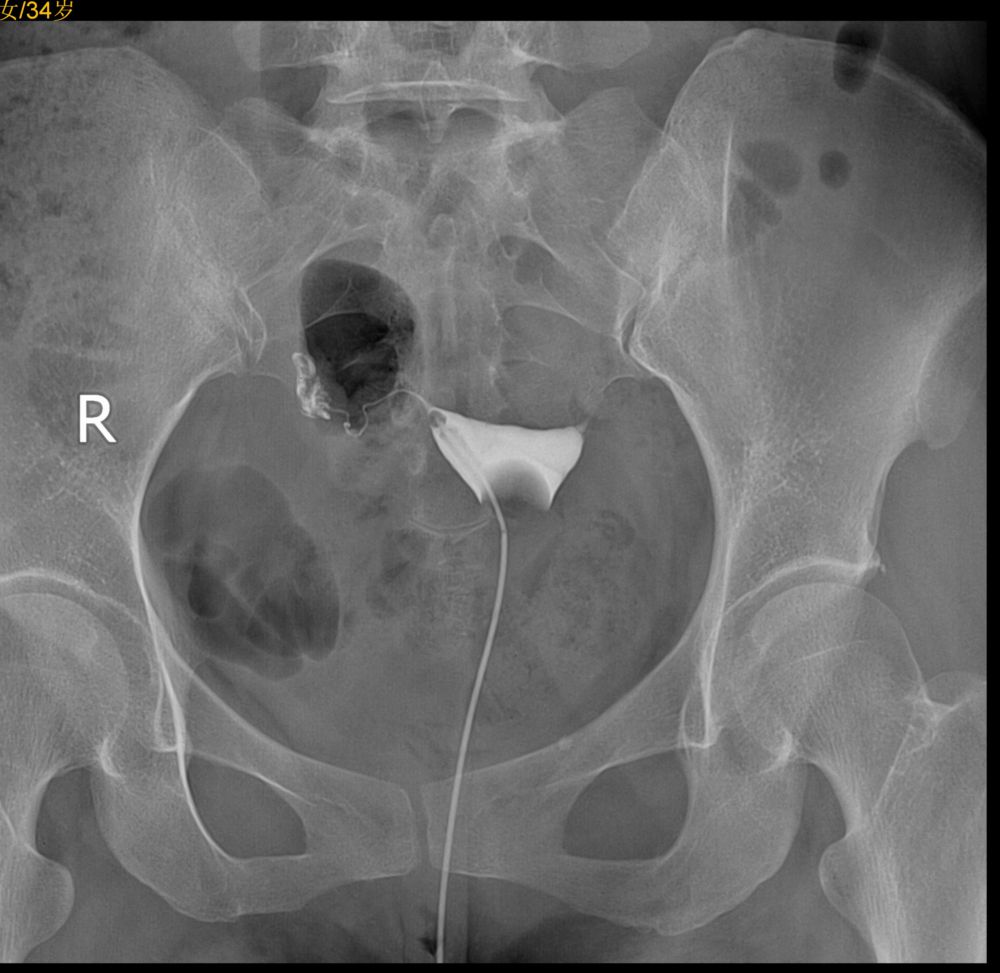

右侧输卵管通,壶腹部粗细不均,右侧宫旁静脉回流,左侧峡部不通,不是是否结扎吻合术后?

左侧输卵管峡部梗阻;右侧宫旁静脉回流。

左侧输卵管不通,右侧输卵管壶腹部粗细不均。

左侧输卵管角部梗阻,右侧宫旁静脉回流

子宫腔规整,右侧输卵管通畅,左侧输卵管阻塞。

左侧输卵管峽部梗阻,右侧宫旁静脉回流。